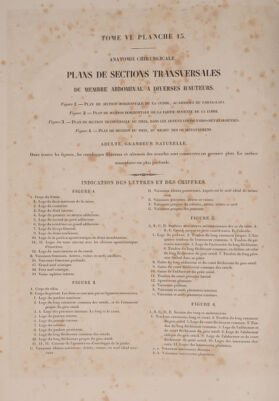

Volume 12

Traité complet de l'anatomie de l'homme comprenant la médecine opératoire ... : avec planches lithographiées ... / par N.H. Jacob.

- Jean-Baptiste Marc Bourgery

- [1831-1854]

Credit: Traité complet de l'anatomie de l'homme comprenant la médecine opératoire ... : avec planches lithographiées ... / par N.H. Jacob. Source: Wellcome Collection.